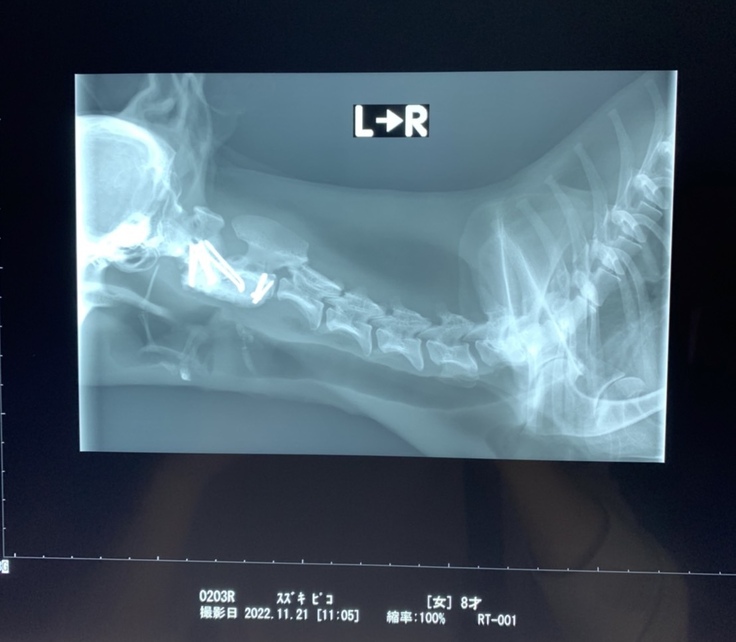

⬛︎レントゲン写真

あんなにもズレていたのが改善されています。

手術の合併症もなくとても順調です😊

█術後のレントゲン写真

術後の状態も安定しており安心しました